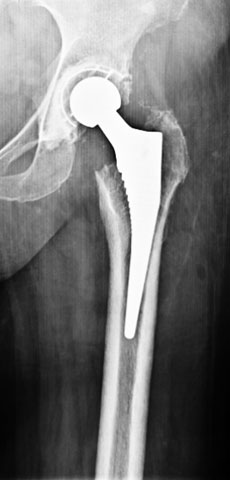

Post surgery

Since the hip joint was normal before the fracture, it was decided (with patient’s consultation) to do a fixation and try and salvage the hip. A closed reduction and percutaneus cancellous screw fixation (minimally invasive) was done.

2 months post surgery

The fracture seemed to be well on its way to heal. She was walking well though still with the walker.